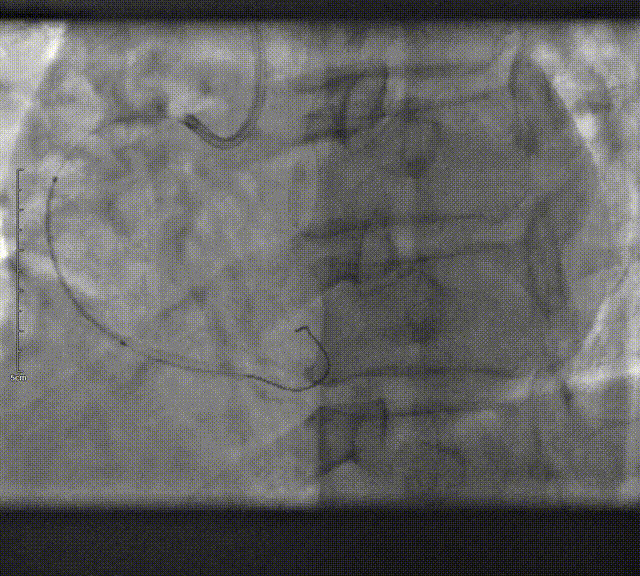

置入6F SAL 1.0指引导管,送入0.014英寸Sion指引导丝跨过狭窄处至RCA远端,Sion-blue送入园锥支远段以保护。

将2.0mm×20mm Maverick球囊送入RCA并定位于远段至近段狭窄处,以8-12ATM×10"扩张,送入2.25mm×33mm药物支架定位于RCA远段段狭窄处,以8ATM×10"扩张。

依次送入2.5mm×33mm、2.75mm×29mm Firebrid2雷帕霉素药物支架定位于RCA中段至开口狭窄处,支架连接处重叠1-2mm,分别以10ATM×10"、12ATM×10"扩张。

复查造影提示远段支架出口以远出现夹层影,遂送入2.25mm×14mm吉威药物支架定位于RCA远段夹层处,以8ATM×10"扩张释放,复查造影提示支架贴壁不良,依次送入2.5mm×8mm、2.75mm×12mm高压球囊定位于远段、近中段支架内处,以12-18ATM×10"后扩张。

复查冠脉造影示血管成形良好,前向血流为TIMI 3级。术毕,术中顺利,术中生命征平稳,病人无不良反应。